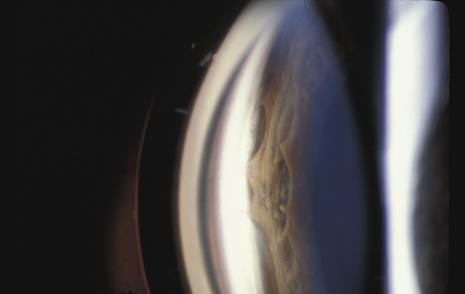

Whatever the mechanism, a portion of the vitreous base can be avulsed from the retina and pars plana. The avulsed base looks like a ribbon floating in the vitreous cavity. Closer inspection reveals that the vitreous base remains in contact with the adjacent vitreous cortex, which is also avulsed (Fig. 15). Avulsion of the vitreous base is pathognomonic of blunt trauma and may have considerable medicolegal importance. Unfortunately, in most cases of severe trauma, the vitreous base does not separate cleanly from the retina and pars plana epithelium. It remains adherent, tearing these tissues. The retina can be torn along the posterior margin of the vitreous base, or the nonpigmented pars plana epithelium can be torn along the anterior margin of the vitreous base, or both can be torn simultaneously. Similarly, if the vitreous is strongly adherent to either lattice degeneration or a vitreoretinal scar posterior to the vitreous base, a posterior flap tear may occur.77 Any of these tears can cause a retinal detachment.

Fig. 15. The avulsed vitreous base remains contiguous with the adjacent vitreous cortex.